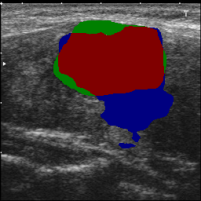

According to Reference 1 and Reference 2 discussed in Sec. 3.2, weakly supervised segmentation requires nodule location labels for location learning and region distribution labels for shape learning. In this section, we integrate geometric transformations of point annotations and segmentation from prompted MedSAM to generate high-confidence location labels for location learning in Eq. (1), as well as high-confidence foreground labels and background labels for shape learning in Eq. (2) and Eq. (3).

Specifically, as illustrated in Fig. 1, in the high-confidence labels generation phase, we derive three geometric transformations representing low-level topological information from clinical annotations:

Connecting the endpoints of the annotations along each axis to form quadrilateral regions.

Identifying and filling the minimum bounding box enclosing these four points per target to create box regions encompassing all foreground pixels.

Negating the bounding box regions results in obtaining background-only regions.

The regions that contain high-level semantic information are generated by prompted MedSAM:

Using MedSAM with prompts computed from point annotations to obtain segmentation masks that reflect anatomical distributions from input images.

Finally, we fuse the initial topological shape ex-rectangle , in-quadrilateral , and out-rectangle and results from prompted MedSAM to generate high-confidence location , foreground , and background labels .

| (4) | ||||

where denotes the logical OR operation applied to the positions of two masks, while represents the logical AND operation.